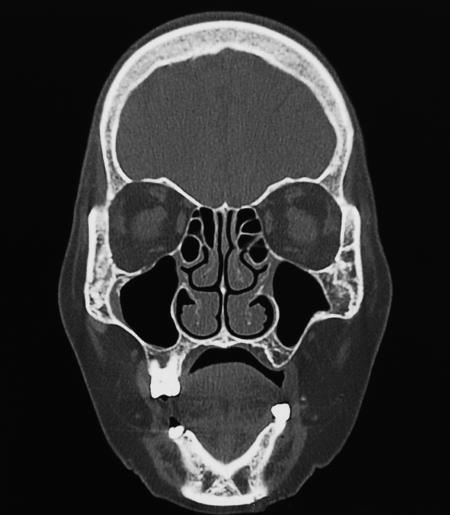

На снимке МРТ (см. рис. 6) видно, что этот человек сейчас хорошо дышит правой ноздрей, там назальные пути шире, а левая ноздря отдыхает.

Рис. 6. Снимок МРТ